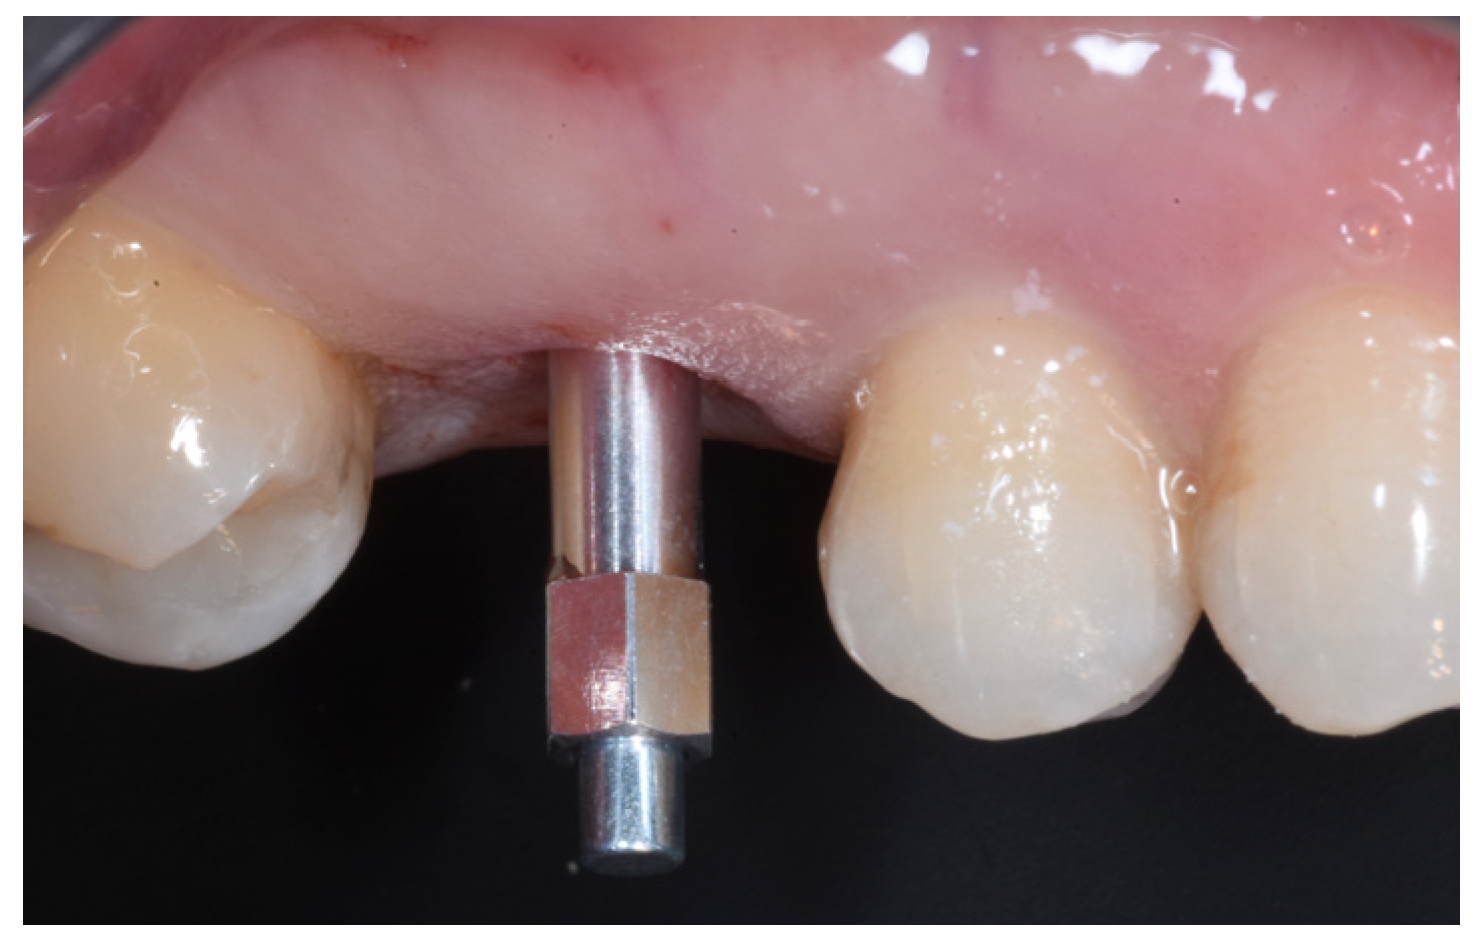

2.6. Case Presentation. Nano-HA Applied to Socket Preservation Procedures

3. Results